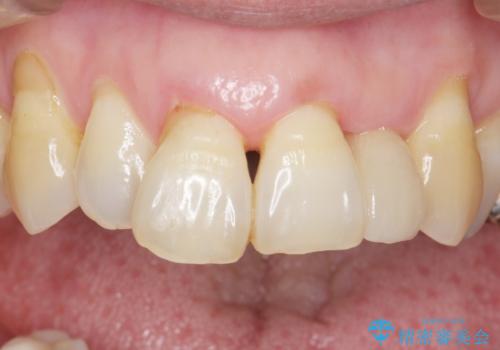

- 下の前歯(左下2)と奥歯の動揺がひどくなってきたことを主訴に来院された患者様です。

精査したところ、前歯の咬み合わせが反対になっていること、下の奥歯(下顎両側67)が4本欠損していることから動揺が生じていました。

入れ歯も抵抗があるとのことから、相談を重ね、今の状態では保存不可能な下の前歯(左下2)を抜去し、ブリッジや連結補綴により動揺を抑えることにしました。

また、咬み合わせが反対になっている上の前歯(左上2)も補綴で形を変えることにより、咬合を改善しました。

気にされていた前歯と奥歯の動揺がなくなったことと自然な仕上がりに喜んで頂けました。